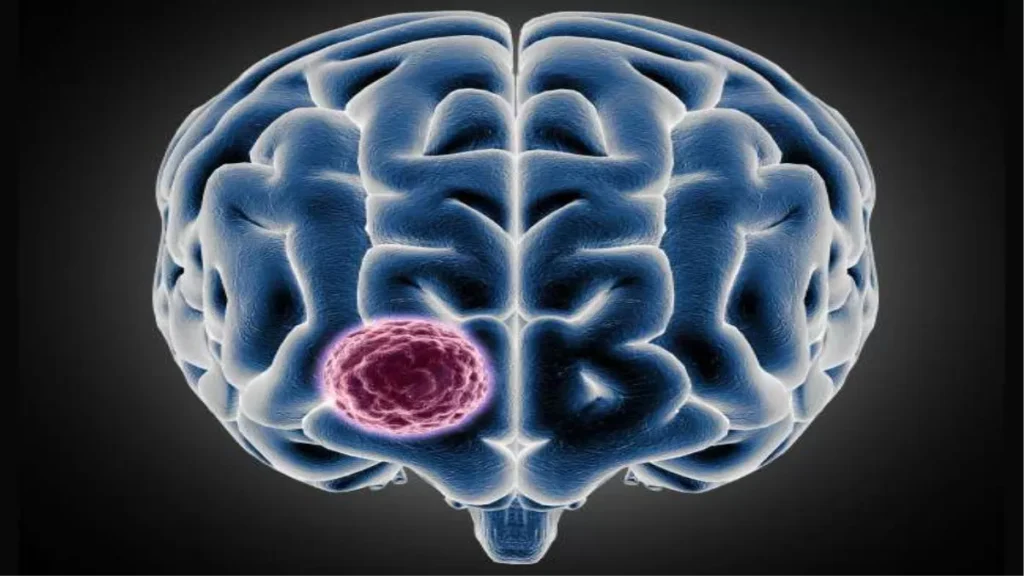

ब्रेन ट्यूमर क्या है?

ब्रेन ट्यूमर मस्तिष्क में असामान्य कोशिकाओं की वृद्धि है, जो धीरे-धीरे दिमाग की कार्यक्षमता को प्रभावित करती है। कई बार यह फेफड़ों, स्तन या किडनी के कैंसर से भी फैल सकता है, जिसे मेटास्टेटिक ट्यूमर कहा जाता है। ऐसे मामलों में इसके लक्षण बिल्कुल ब्रेन कैंसर जैसे नजर आते हैं।